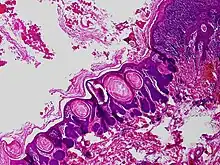

Trichofolliculoma is a cutaneous condition characterized by a benign, highly structured tumor of the pilosebaceous unit.[1][2] Trichofolliculoma is a rare tumor of the eyelid. It can be suspected by the “cotton bag sign”[3]